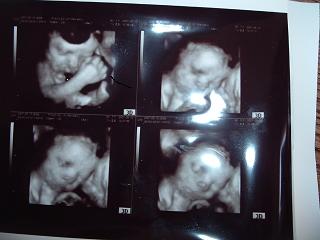

Győrffy csinálta! Én is nagyon örültem, hogy ilyen jó lett, eddig mikor a srácokkal voltam alig lehetett valamit látni. Most szerencsém volt végre